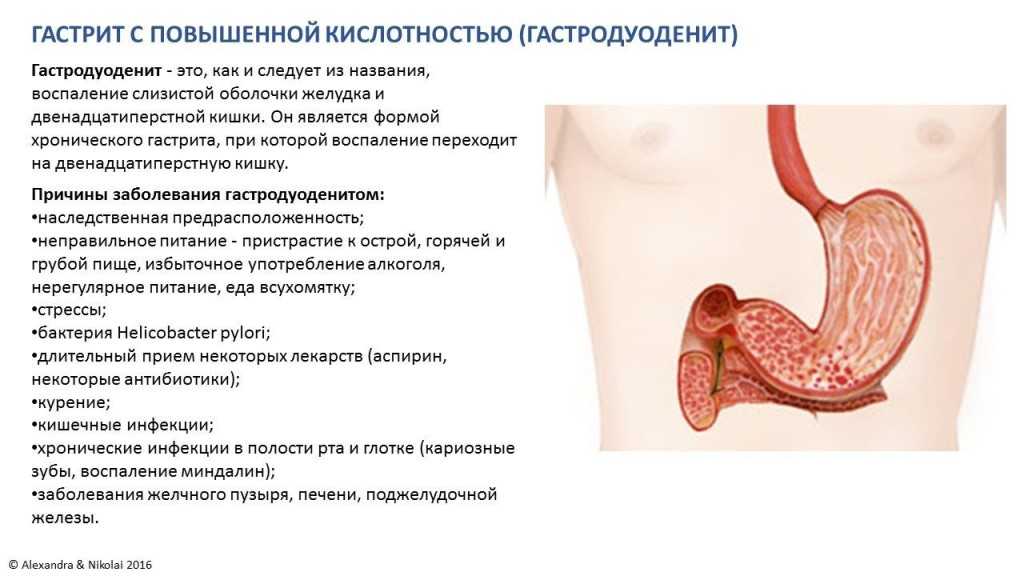

Информация и фотографии о хроническом гастрите и дуодените

Раздел: Фотодневник открытий